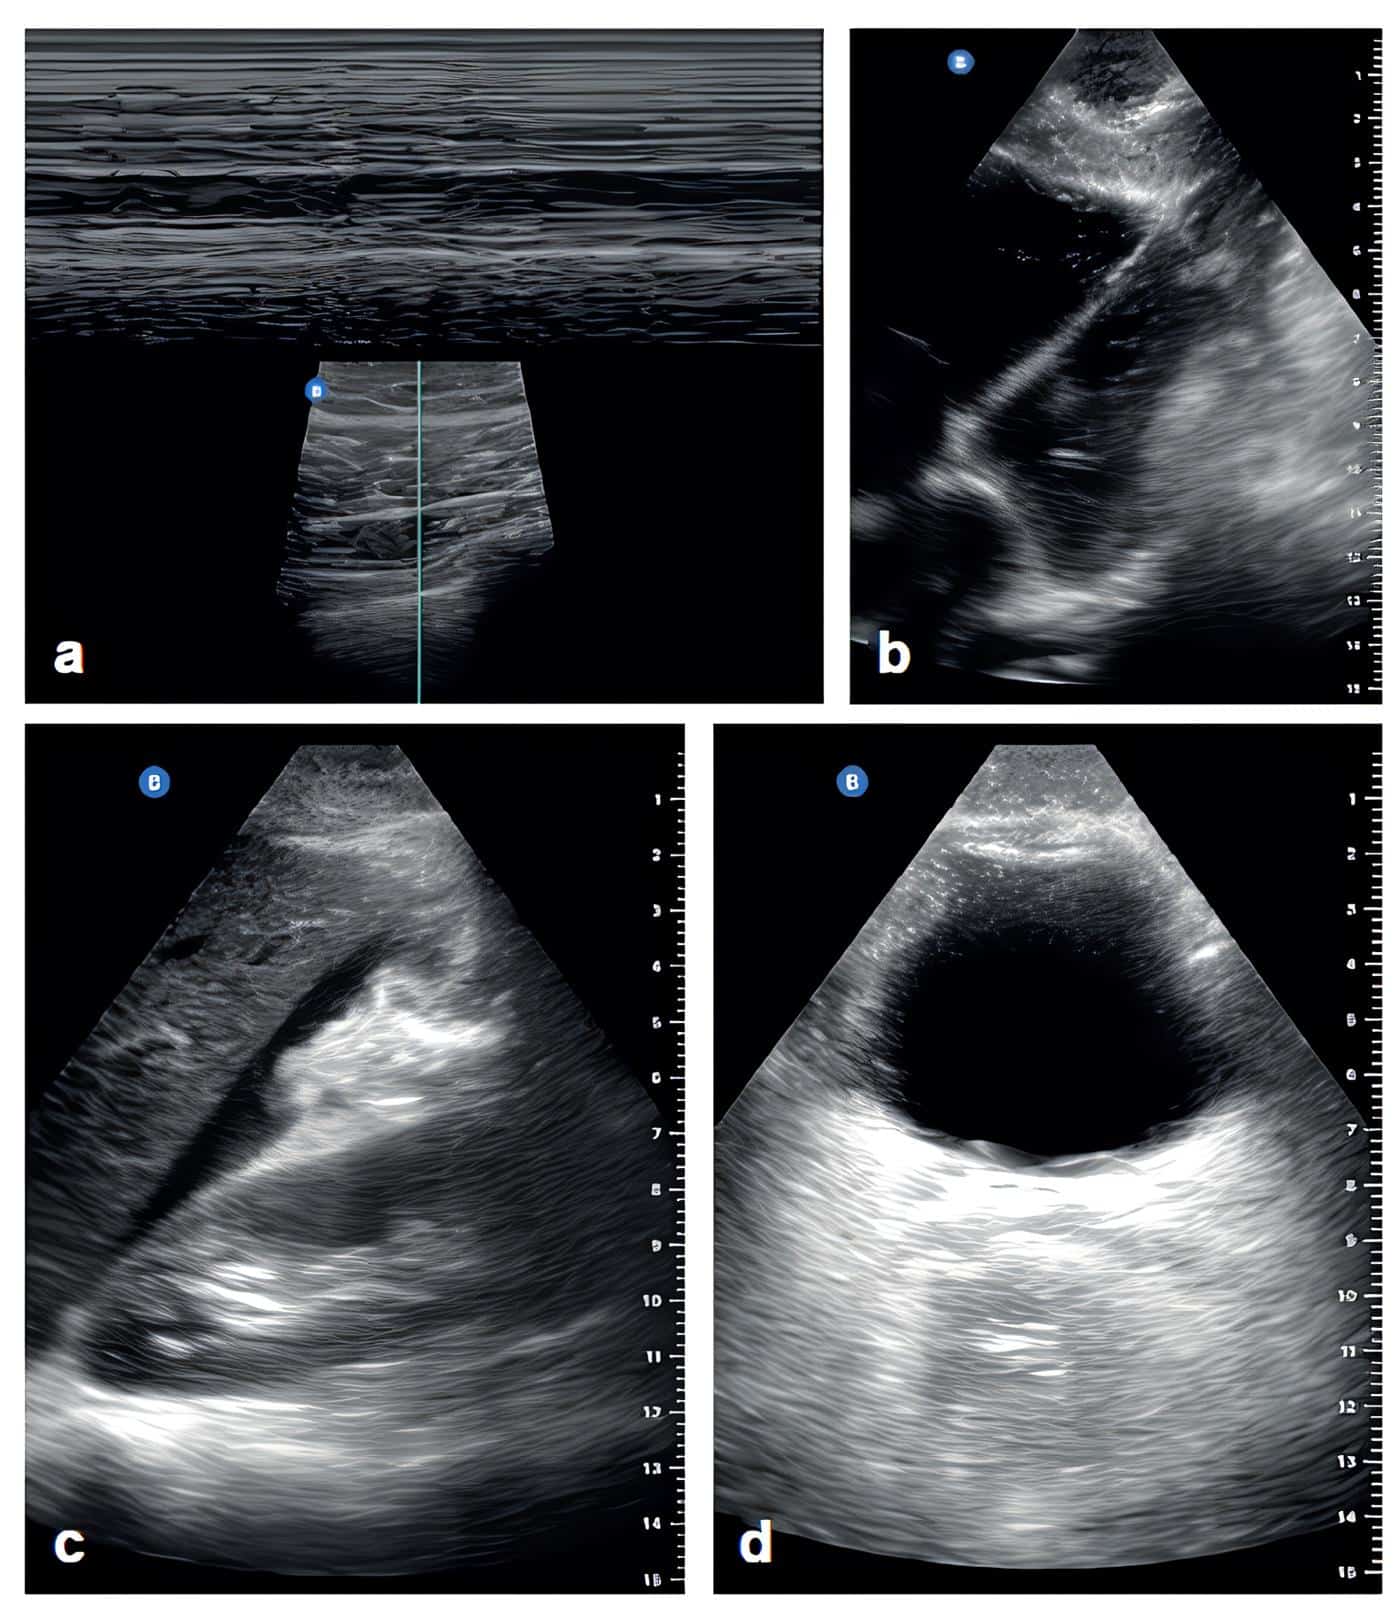

The main mechanism of trauma was penetrating (n=32; 69.5%), 93.4% (n=43) were taken to the operating room, mainly performing emergency laparotomy (n=24; 52.1%); 37 (80.4%) patients had positive E-FAST (Figure 1), 97% (n=35) were found to be true positive, based on intraoperative findings (only two were false positive). Of the nine (19.5%) patients with negative E-FAST, five underwent surgery, with three having positive findings of free cavity fluid (false negative) (Table 1).

Figure 1. Findings with the use of E-FAST protocol using the portable ultrasound machine (Butterfly iQ+, Butterfly Network Technologies, USA). a. M-mode barcode sign, linear lung scan; b. Subxiphoid ultrasound showing four-chamber cardiac window; c. Morrison’s pouch ultrasound with positive identification of free fluid; d. Transverse suprapubic ultrasound showing four-chamber cardiac window. Subxiphoid ultrasound showing the four-chamber cardiac window.